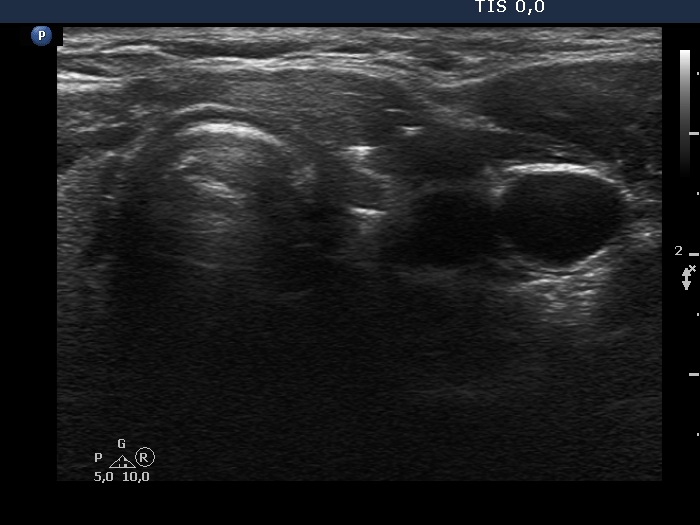

Case 856 (ultrasonographic picture 5)

Left lobe, transverse scan. There is a tiny, deeply hypoechoic mass within less hypoechoic environment. At this time, it is not evident whether this mass is part of the regenerative tissue or corresponds to the thyroid' remnant.